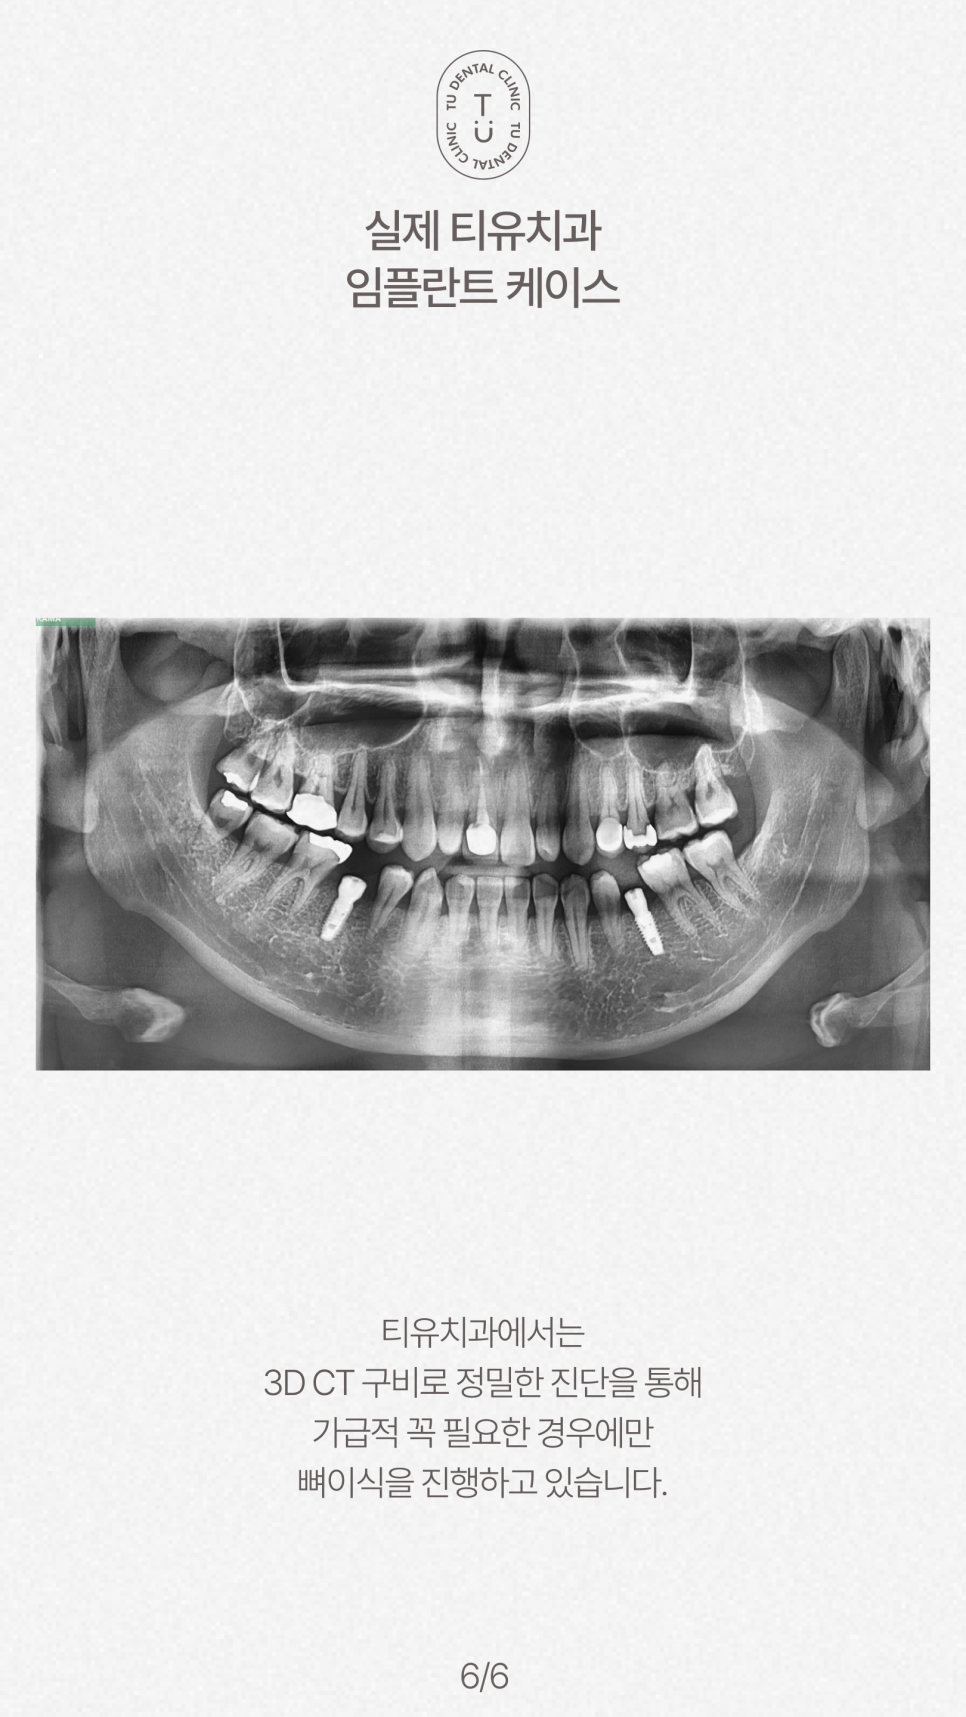

*해당 파노라마 사진은

티유치과에서 실제로 진행한

뼈이식 없이 수술한 임플란트 케이스입니다.

티유치과에서는

숙련된 의료진, 정밀한 진단을 통해

꼭 필요한 경우에만

뼈이식을 진행하고 있습니다.

다양한 임상 케이스를 경험한

숙련된 의료진과

3D CT, 스캐너 구비 등 정밀한 진단을 통해